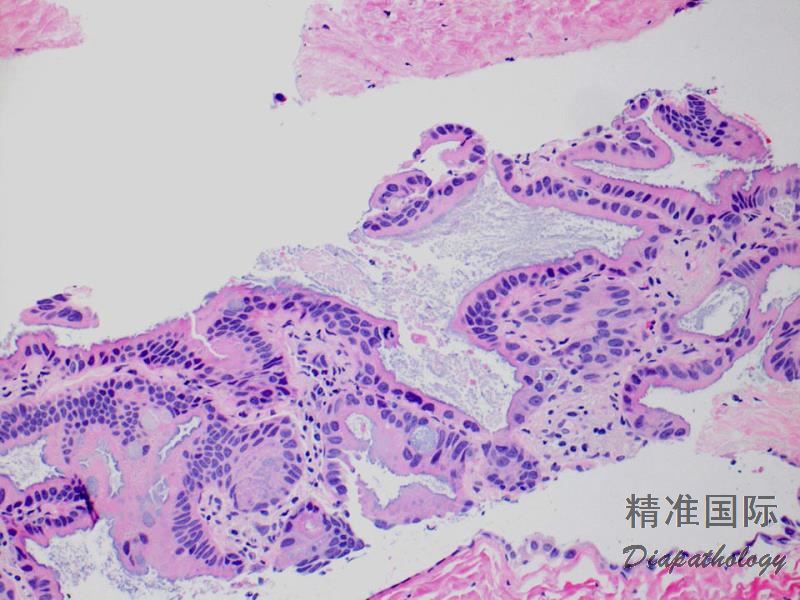

肿瘤细胞呈杯状或高柱状,胞浆黏液丰富;

细胞异型不明显或无异型,核小,位于细胞基底部;

腺泡内常含黏液;

可包含其它成分如贴壁生长、腺泡、乳头、微乳头、实性生长;